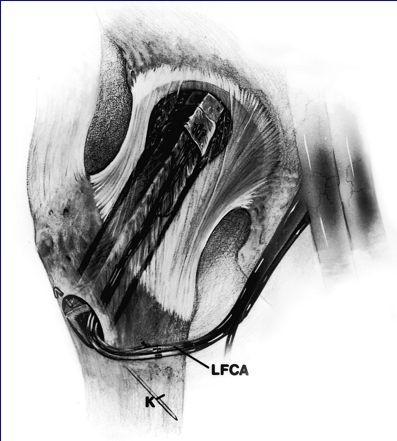

Injerto de Peroné  descompresión de la cabeza femoral.  resección del hueso necrótico.  sustitución con hueso esponjoso fresco.  soporte del hueso subcondral con un injerto óseo fuerte y viable.  revascularización y osteogénesis de la cabeza femoral

El injerto peroneal con los vasos peroneos se obtiene de la pierna ipsilateral para insertarlo en el cuello y cabeza femoral.

Se obtiene hueso esponjoso del trocánter mayor que se inserta en la cavidad formada tras la extirpación del hueso necrótico. El injerto de peroné se inserta en el túnel y se estabiliza con una aguja de Kirschner de 0.62 mm. La arteria y venas peroneas se anastomosan a las ramas ascendentes de la arteria circunfleja femoral lateral (LFCA) y sus venas satélites.

Injerto de Peroné